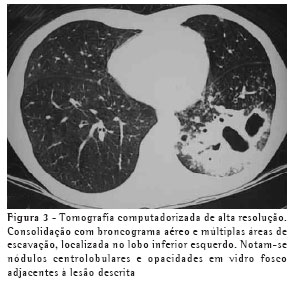

O achado de imagem mais freqüente, presente nos 7 pacientes, foi consolidação de contornos mal definidos (Figuras 1, 2, 3 e 4), sendo que 5 deles tinham broncograma aéreo de permeio, principalmente na periferia da lesão. Em 3 casos, a consolidação organizava-se sob forma de massa. Em 6 dos 7 pacientes foram observadas, no interior das consolidações, áreas irregulares de escavação, múltiplas em 5 e única em 1 paciente. Em um dos casos não se observou escavação, mas ele mostrava áreas hipodensas de permeio, sugestivas de necrose (Figura 5). Apenas um dos pacientes apresentou nível líquido no interior das cavidades.

Opacidades em vidro fosco foram vistas em 6 pacientes, localizadas predominantemente ao redor das lesões escavadas, não sendo, em nenhum dos casos, achado predominante.

Pequenas opacidades nodulares centrolobulares e padrão de árvore em brotamento foram vistos em 3 pacientes, com distribuição predominantemente ao redor da área de consolidação. Em 1 destes pacientes estas lesões foram encontradas também nas porções pendentes dos lobos inferiores. Nódulos do espaço aéreo, tendendo a confluência, localizados na periferia das consolidações pulmonares, foram vistos em 4 casos.

Outros achados foram as opacidades em vidro fosco, os nódulos do espaço aéreo, os pequenos nódulos de distribuição predominantemente centrolobular, e o padrão de árvore em brotamento. Eles se localizavam predominantemente ao redor das consolidações escavadas, sendo que em um dos casos também estavam presentes em ambos os lobos inferiores. Acredita-se que tal achado deva representar disseminação broncogênica da infecção.